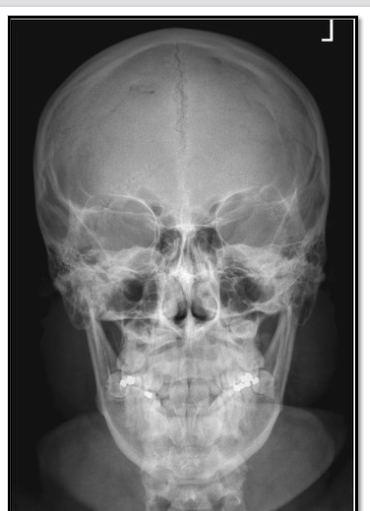

44

critique

petrous too low, by 10 deg (neck is extended) OML not perpendicular